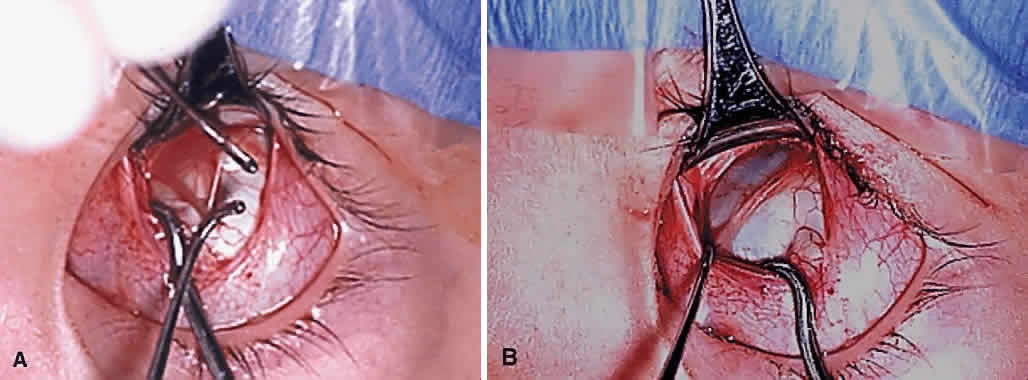

The superior oblique tendon is drawn forward through the surgical wound and attachments to Tenon's fascia and the superior rectus muscle are cut. A second pass of the muscle hook helps ensure that no fibers have been missed. Gross assessment of tendon laxity is then performed. A lax tendon requires a greater amount of tuck, whereas a normal tendon should be approached with caution, and a taut tendon should not be shortened at all. A Bishop tendon tucker is helpful to control the isolated tendon and permits the surgeon to quantitate the amount of tendon shortening conveniently. The tendon is drawn in the tucker until snug, but not tight. The loop of tendon is then sewn to itself using a nonabsorbable suture such as 5-0 braided Dacron. After this provisional tuck has been completed, the tendon is released into the orbit and a traction test is performed with the eye positioned in maximum adduction. It has been our experience that the ideal tuck results when the amount of tendon shortening produces its first resistance to elevation as the inferior limbus crosses an imaginary line between the medial and lateral canthus (Fig. 7).34,51 Care must be taken not to retropulse the globe into the orbit, because this exaggerates the duction limitation. An average tendon shortening of approximately 12 mm is required in congenital superior oblique muscle palsy (lax tendon) and 8 mm in acquired palsy (normal tendon). However, the optimum amount of tuck does not necessarily correlate with the size of the hypertropia in primary gaze position and intraoperative titration is essential. If the initial tuck is too tight or too loose based on results of traction testing, the tendon is retrieved from the orbit and the tuck is adjusted. The final tie-off is performed by passing the suture through and around the superior oblique tendon a second time after which it is tied securely. This minimizes the potential for tendon slippage through the tuck and provides additional security should a suture loop fail postoperatively. It is not necessary to sew the redundant tendon to the sclera. Conjunctival closure is performed at the surgeon's discretion. A running suture of 6-0 plain catgut is well tolerated and prevents the conjunctiva from gaping open postoperatively.

Serious complications of superior oblique muscle strengthening are infrequent. Intraoperative complications relate primarily to orbital hemorrhage from injury to a vortex vein or unintended entry into the orbital fat space, which results in an adherence syndrome with restricted ductions postoperatively. These can be avoided by good surgical exposure, use of loupe magnification with a surgical headlight, and deliberate and meticulous surgical technique. The superior oblique tendon can be surgically missed or inadvertently cut during dissection of the intermuscular septum. Anatomic variations including absence of the tendon are common.12 Confusion can also occur if the surgeon inadvertently engages the superior oblique tendon when first attempting to hook the superior rectus muscle.49 However, this is less common when the superior oblique tendon is approached temporally rather than nasally (Fig. 9). Surgical overcorrection occurs frequently, but it is fortunately not permanent in most patients. However, permanent overcorrection that results in a primary gaze position hypotropia is usually an unacceptable result and requires reoperation. It can be caused by excessive surgical dosage, spontaneous recovery of superior oblique muscle function, or failure to recognize bilateral superior oblique muscle palsy preoperatively.